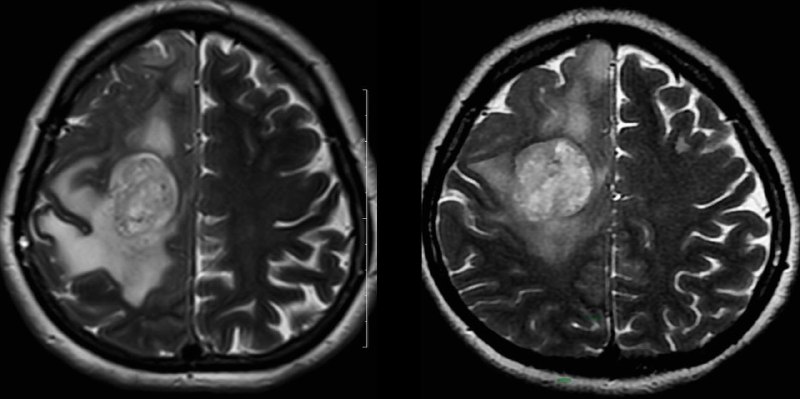

Глиобластома.

Разница в две недели.

Отек стал меньше из-за стероидов.

Но растет быстро, сволочь…